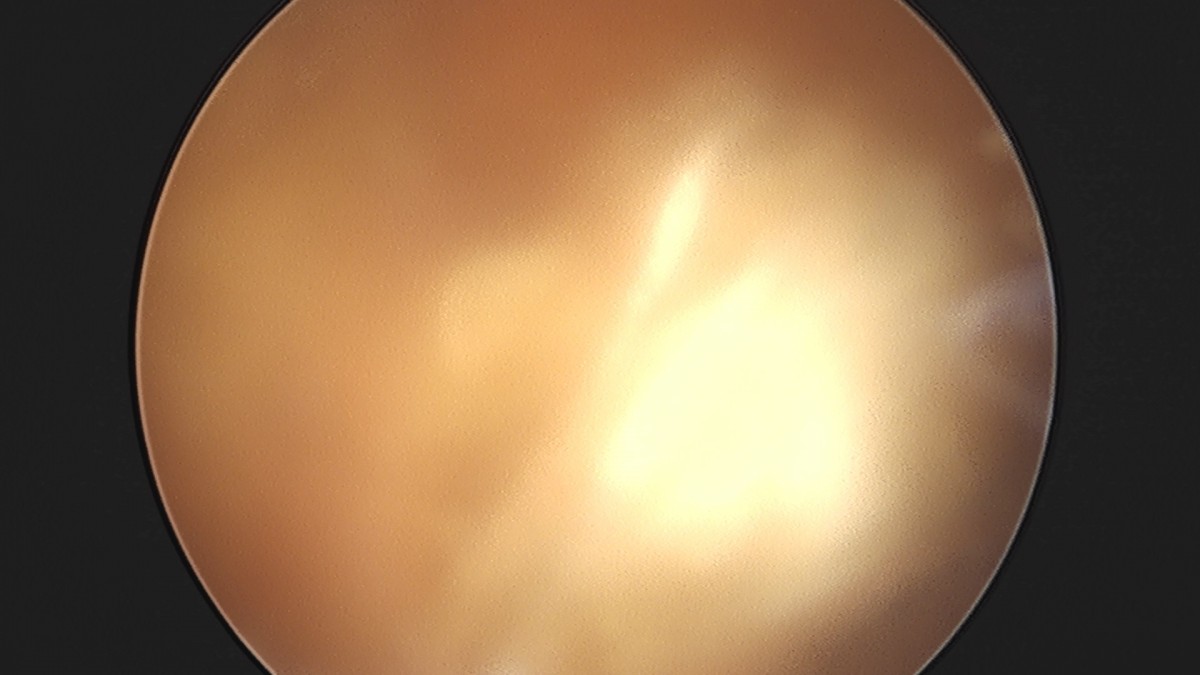

이재상원장님 무릎 전방십자인대 재건술 김태O 환자

작성자 최고관리자 댓글 0건 조회 679회 작성일 25-09-16 16:23